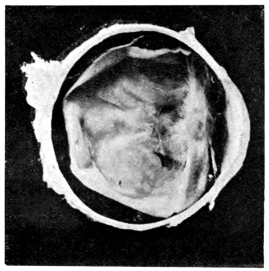

PLATE IV.

22.

LENS DISLOCATED BEHIND RETINA

curly bracket span

48

23.

FISTULA OF THE CORNEA

24.

CAPSULO-CORNEAL SYNECHIA

25.

RETINO-CORNEAL SYNECHIA

26.

SCLERAL FISTULA

27.

"    " (MAGNIFIED)